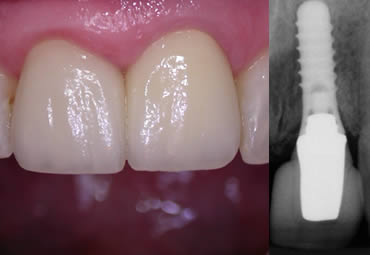

Implant used to replace upper front tooth - notice the excellent colour match between the original teeth and the implant

Implant crown replacing upper front tooth